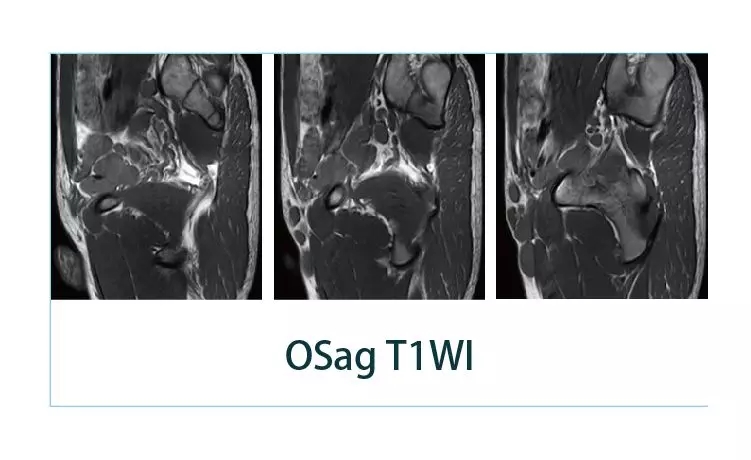

【朗润影像档案】20190426磁共振影像病例结果讨论

【朗润影像档案】磁共振影像病例分享(编号20190426)